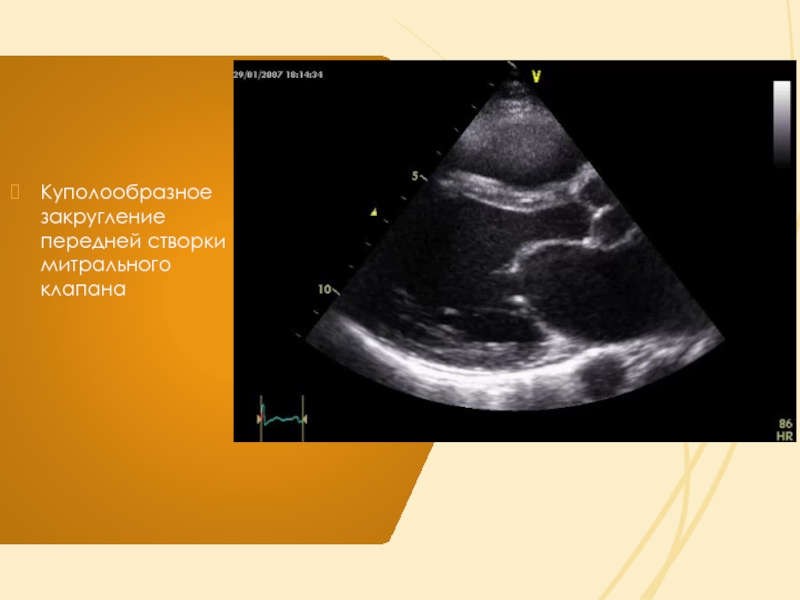

Слайд 14Куполообразное закругление передней створки митрального клапана

Куполообразное закругление передней створки митрального клапана